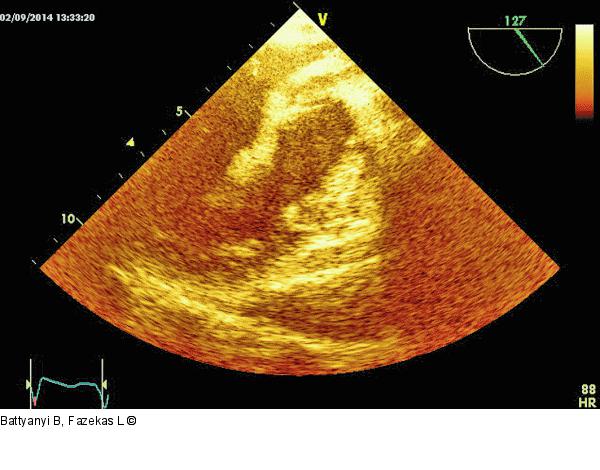

Abbildung 7: Thromboembolus Thromboembolus in der linken Herzhöhle. Im Gegensatz zu Abb. 6 ist dieser Thrombusteil schmaler, inhomogener. |

Thromboembolus in der linken Herzhöhle. Im Gegensatz zu Abb. 6 ist dieser Thrombusteil schmaler, inhomogener. |